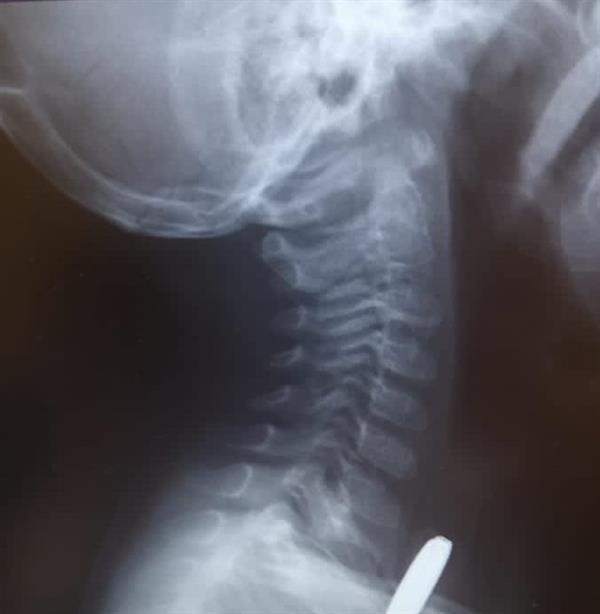

وكانت الطفلة قد وصلت إلى المستشفى وهي تعاني من عدم القدرة على البلع وتناول الطعام بشكل طبيعي، وبعد إجراء الفحوصات اللازمة لها أظهرت النتائج وجود جسم غريب في المريء.

وعلى الفور نُقلت الطفلة إلى غرفة العمليات، وتم إجراء منظار تحت التخدير العام واستخراج البطارية من المريء، ومتابعة حالتها في العناية المركزة حتى استقرارها.